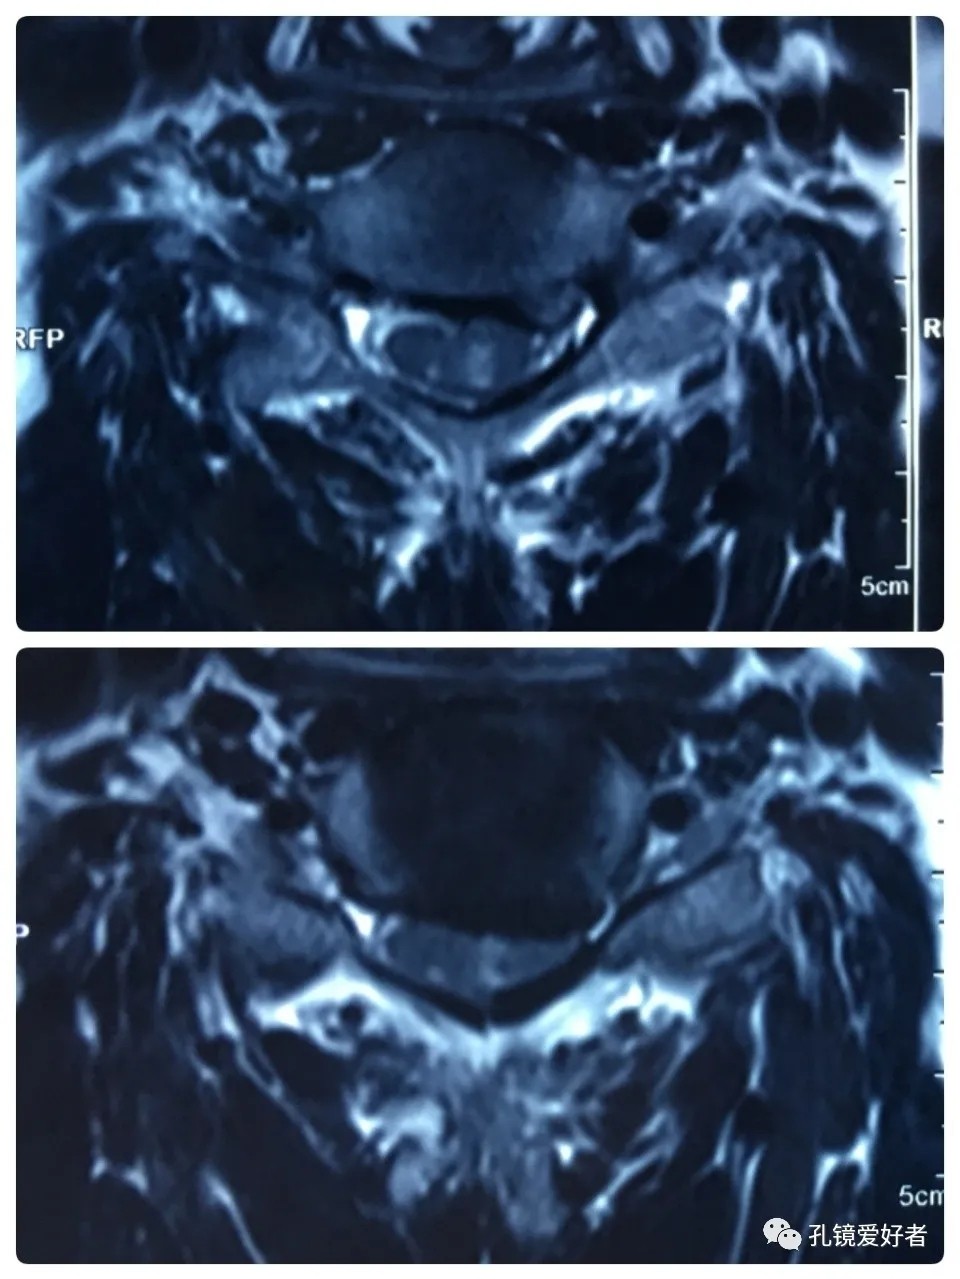

The patient's preoperative imaging data

The MRI shows that the cervical stenosis is on C3-4, C5-6 and C6-7. Considering the patient's clinical symptoms, C5-6 and C6-7 are the main affected segments. So it’s advised that the patient  undergo posterior cervical open-door laminoplasty. According to the patient, he had visited many hospitals before and received similar proposals of diagnosis and treatment- posterior cervical open-door laminoplasty. The reason he came to our hospital was that he wanted his surgery could be performed in a minimally invasive way. After considerable preoperative discussion with my colleagues and the patient, we decided to perform the minimally invasive endoscopic decompression for C5-6 and C6-7 double-segment stenosis through posterior approach (with the Delta system).